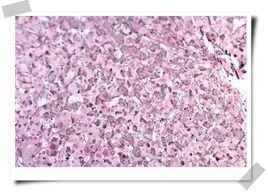

(4肝功能檢測可有谷丙轉氨酶(GPT)反覆異常,濁度和絮狀試驗持續升高,血漿白蛋白減少,球蛋白增加,蛋白比值異常,血清蛋白電泳Υ-球蛋白明顯增加,血沉也可加快。此外還可出現抗平滑肌抗體、抗線粒體抗體及類風濕因子、狼瘡細胞、抗肝細胞膜脂蛋白陽性等自體免疫反應現象。慢性活動性肝炎病人,有的臨床症狀並不典型。對那些隱慝發展長期不緩解,澳抗持續陽性,肝功能損害雖輕但有日趨嚴重傾向者,應做肝穿活檢,以明確診斷,及時治療。此型肝炎與慢性遷延性肝炎相比,症狀重,預後差,只有15~30%的患者經治療痊癒,相當多的患者經積極治療後病情可穩定較長時間,但也有少數患者因種種原因難以緩解,而使病情進一步惡化,最後導致肝硬化。所以,病人應較長時間處於醫療監護之下,以便取得滿意的療效